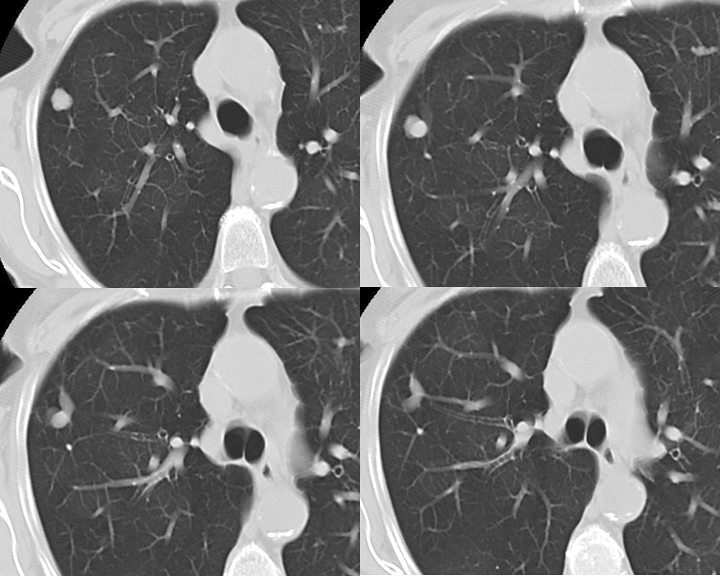

COPD

muc plugs CT